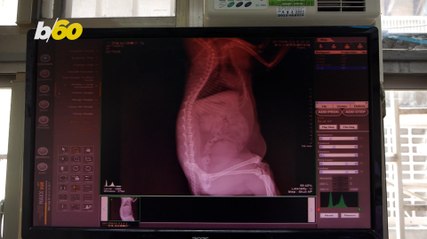

X Ray Machine That Sees Through Clothes